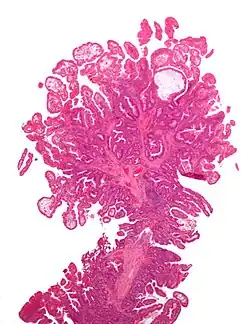

Hyperplastic polyp 0% No dysplasia.[10]

• Mucin-rich type: Serrated ("saw tooth") appearance, containing glands with star-shaped lumina.[11] Crypts that are elongated but straight, narrow and hyperchromatic at the base. All crypts reach to the muscularis mucosae.[11]

• Goblet cell-rich type: Elongated, fat crypts and little to no serration. Filled with goblet cells, extending to surface, which commonly has a tufted appearance.[11]